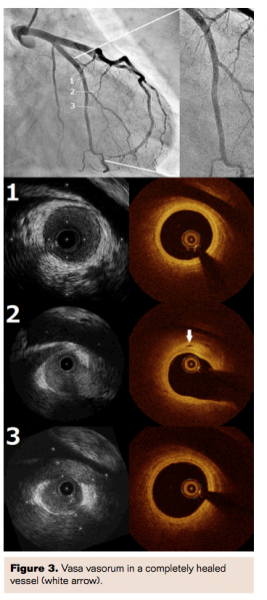

Lack of symptoms, ST-segment elevation, or coronary flow disturbance led to selection of conservative therapy. The patient was treated with aspirin, imidapril, carvedilol, and pravastatin, and she completed a cardiac rehabilitation program uneventfully with no examinations showing fibromuscular dysplastic lesions in the renal, iliac, carotid, or cerebral arteries. One-month follow-up CAG revealed healing of the SCAD findings with a restored normal coronary flow. Intravascular ultrasound (IVUS; Atlantis SR Pro2, Boston Scientific) and optical coherence tomography (OCT; ILUMIEN OCT Imaging System, St. Jude Medical) demonstrated a double-lumen morphology or an image of intimal flap with an intramural hematoma, which established the diagnosis of SCAD of the LCX with insignificant compression of the true lumen, which supported the strategy of conservative therapy (Figure 2). Seven-month follow-up CAG, IVUS, and OCT demonstrated a complete resolution of the above SCAD findings (Figure 3), resulting in a diagnosis of complete healing of the SCAD. Serial echocardiography calculated EF of 62% at 1 month and 66% at 7 months.

While the usefulness of IVUS and OCT to detect SCAD has been well known, the serial follow-up of SCAD resulting in complete healing has not been reported. Spontaneous coronary artery dissection is a rare cause of ACS frequently seen in young women without coronary risk factors. Although the most common conditions associated with SCAD are considered to be coronary atherosclerosis and the peripartum period, a recent study suggests FMD may also be associated with it. However, the details of the cause as well as prognosis or treatment including emergency revascularization and long-term pharmacological therapy are not yet clearly defined. In terms of emergency treatment for SCAD, revascularization should be applied if ongoing ischemia is detected, which is very similar to atherosclerotic acute coronary syndromes. In contrast, according to a recent study showing that percutaneous coronary intervention for SCAD in an emergency setting is often complicated by technical failure especially in crossing a wire, conservative approach would be a choice for those without ongoing ischemia.1 Based on this evidence, we decided to treat this particular case conservatively. On the other hand, we need to consider that in case of extremely high-risk anatomy such as left main coronary artery involvement, aggressive revascularization strategy should be applied. Based on reports from Alfonso et al that SCAD may spontaneously heal at long-term follow-up,3 we performed CAG, IVUS, and OCT at 7 months again, which demonstrated complete healing of SCAD. To the best of our knowledge, this is the very first reported case of spontaneously healed SCAD with unique intracoronary images. Intravascular ultrasound and OCT could not detect an entry point of SCAD at 1-month follow-up, possibly because the intimal tear had already healed. In our particular case, a vasa vasorum was detected in a completely healed vessel wall where dissection had existed. These findings may support a hypothesis that hemorrhage of vasa vasorum is responsible for SCAD.3